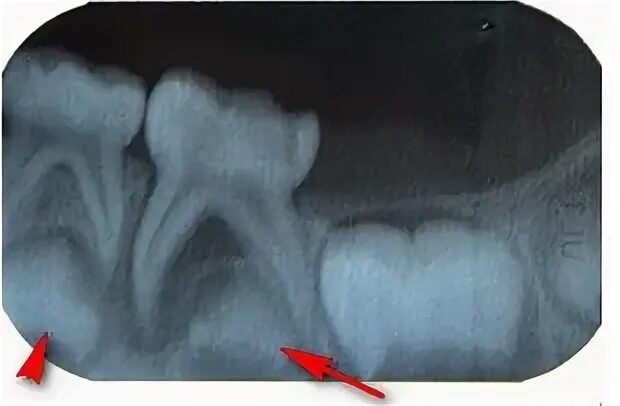

У ребенка нет зачатка постоянного зуба